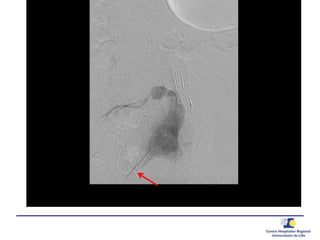

Ponction translombaire –

embolisation directe

Ponction

Anévrysmographie

Guide de pression 0.014’’

20 G needle0.014’’ PressureWire

 Pression

Aorta

Sac